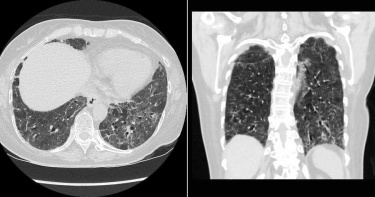

肺部纖維化多可怕?染疫病患重症「無法脫離氧氣罩」 醫喊話:趕快打疫苗

新冠肺炎爆發至今將近2年,全球持續對抗疫情,不少確診案例出現「肺部纖維化」的症狀,病患可能會因為呼吸衰竭導致死亡。對此,胸腔科醫師蘇一峰曝光確診重症病患的照片,看了讓人怵目驚心,因此他喊話:「趕快打疫苗!」蘇一峰在臉書PO文,貼出感染新冠肺炎重症後,肺部纖維化的照片,因為出現在院內自己人身上,讓他非常難過。更提到,昨天打了好幾通電話想辦法,但病人目前仍無法脫離氧氣,他也向第一線人員喊話:「高危險醫護人員趕快打疫苗,不想肺纖維化就趕快打疫苗」。確診重症病患的肺部X光。(圖/翻攝自蘇一峰臉書)病患肺部出現纖維化。(圖/翻攝自蘇一峰臉書)網友看完都十分擔心,紛紛留言:「難過!祈福,早日康復」、「好嚴重,祝平安度過危機」、「醫師辛苦了,疫苗接種重要」、「還沒完整施打的醫護真的要盡速施打」、「希望大家都能順利接種疫苗,趕快恢復正常生活!也不要浪費疫苗!」事後,蘇一峰補充:「很多醫護人員第一劑打AZ,要等兩個月以上才能打第二劑AZ有的人等待的中間就被感染了…AZ混打mRNA疫苗中間只需隔一個月,保護力就可以等同mRNA兩劑,真的不能考慮看看嗎…」,同時PO出瑞典混打研究刊登在NEJM,「AZ混打莫德納後,產生的有效中和抗體濃度是10倍以上!混打的副作用較高,但是沒有達到統計學上有意義的增加!」他表示很期待台大AZ莫德納的混打研究,只是還要再等2個月。蘇一峰希望疫苗可以混打。(圖/翻攝自蘇一峰臉書)